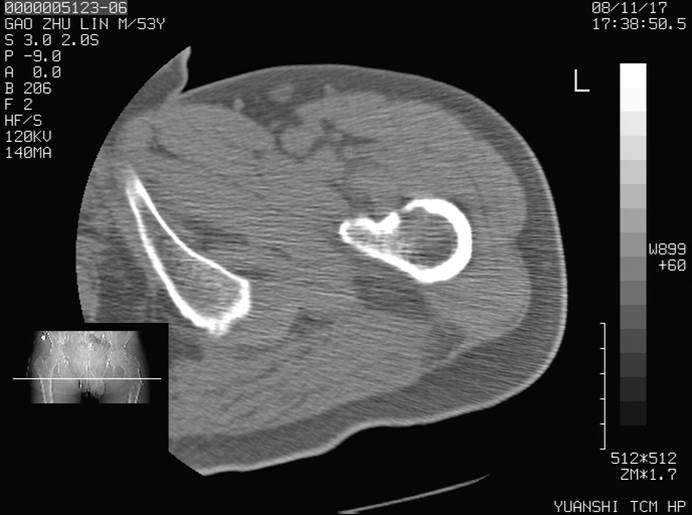

标题: CT16696:M53Y,左股骨上段骨折。 [打印本页]

标题: CT16696:M53Y,左股骨上段骨折。

左股骨上段外伤1个小时,左股骨上段疼痛。村医以腰椎间盘病变给以按摩及理疗数天。

图像不太清楚,左股骨上段外伤性骨折?病理性骨折?

左股骨上段粉碎性骨折

左股骨上段粉碎性骨折;建议上传骨窗看看是不是病理性的啊!

左股骨上段粉碎性骨折,不排除病理性骨折可能。

考虑骨肉瘤伴病理骨折

考虑:骨肉瘤伴病理骨折.

病理性骨折,考虑转移所致.

左股骨上段粉碎性骨折,不排除病理性骨折可能